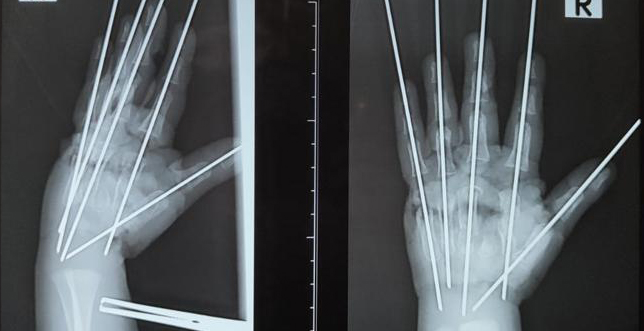

– Травма очень тяжёлая, что обусловлено раздавливающим механизмом мясорубки. Повреждена была вся кисть, раздроблены кости, сухожилия, сосуды, нервы. Фактически имела место ампутация – кисть держалась на нескольких связках. Нашей задачей было сохранить жизнеспособные ткани, восстановить анатомию конечности и кровообращение, –  сообщил врач.

В ходе операции специалисты Педиатрического университета буквально собрали по частям травмированную руку мальчика.

– Мы выполнили металлоостеозинтез, чтобы соеденить осколки костей. Затем было необходимо восстановить кровоснабжение кисти, – рассказал Антон Волков.

Ребёнку потребовалась аутовенозная пластика: размозженный участок  локтевой артерии хирурги заместили фрагментом подкожной вены пациента. Медики отметили, что после этого пальцы ребёнка стали понемногу розоветь.